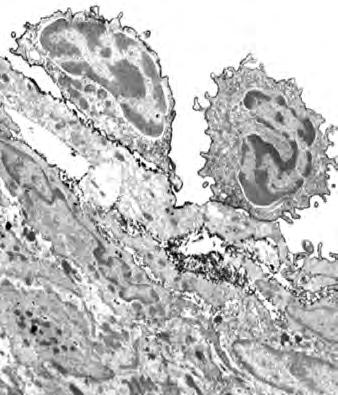

Rak krwi (białaczka)

Obraz komórki białaczki pod mikroskopem elektronowym. Nieustanne uwalnianie enzymów trawiących kolagen symbolizują czerwone “pacmany”.

75 II. Przełom medyczny w opanowaniu raka metodami naturalnymi

Rysunek na sąsiedniej stronie przedstawia przekrój mikroskopowy wątroby pacjenta chorującego na białaczkę limfatyczną.

Każda z małych fioletowych kropek widocznych na zdjęciu to pojedyncza biała krwinka (w tym przypadku limfocyt), która zaatakowała tkankę wątroby (obszar w kolorze różowym).

Zważywszy na wielką liczbę tych fioletowych kropek oraz produkowane przez nie ilości enzymów trawiących kolagen, łatwo sobie wyobrazić, jak wielkie mogą być uszkodzenia tkanki łącznej oraz wyniszczenie organu, spowodowane tym typem raka.

Białaczka jest dobrym przykładem tego, jak zrozumienie mechanizmów komórkowych, takich jak produkcja enzymów trawiących kolagen przez białe ciałka krwi, pomaga w znalezieniu skutecznych rozwiązań terapeutycznych.

Białaczka pod mikroskopem

Białe ciałka krwi pacjenta chorego na białaczkę (limfocyty) zaatakowały wątrobę. Olbrzymie ilości produkowanych przez nie enzymów trawiących kolagen niszczą organ, w konsekwencji prowadząc do jego niewydolności.

77 II. Przełom medyczny w opanowaniu raka metodami naturalnymi

Zdjęcie mikroskopowe białaczki limfatycznej.